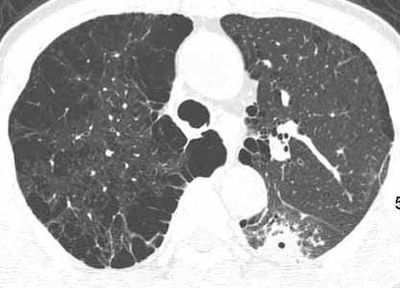

球形肺炎:病变密度相对较淡,中央密度略高,ct图片上密度较为均匀,增强中央可出现无强化区。病变邻近胸膜反应较为显著,可表现为增厚、粘连(可以比较广泛),病变内可以见到大血管的贯穿,周围及近肺门侧可以见到血管纹理增多、增粗,可有支气管充气征象,两侧可垂直于胸膜或呈方形,边缘可为刀切征,它可以出现毛刺样的类似改变,短期内抗炎治疗有效。

球形肺炎是大叶性肺炎的一种特殊表现[1],以肺的渗出实变为主。它的机理未明,可能是由于抗生素的广泛应用,大叶性或节段性肺炎发展受到限制而形成球形,其形成又与病缘菌的毒性数量及机体的免疫能力有关。病人多有感然症状,某些病人无明显感然症状。病变呈球形或椭圆形,大小不等,病灶密度多均匀,ct值稍低于软组织密度;或中央密度高,边缘密度低,显示晕圈状改变;有时可见空洞[2]。病灶边缘比较规则,也可不规则,有毛刺或呈锯齿状改变,但较模糊。位于肺周区,贴近胸膜,部分病栽表现为两侧缘垂直于胸膜,呈刀切样平直边缘。病灶周围血管纹理增多、增粗、常有局限性胸膜增厚。球形肺炎抗炎两周后,病灶即有缩小,最后能完全吸收。